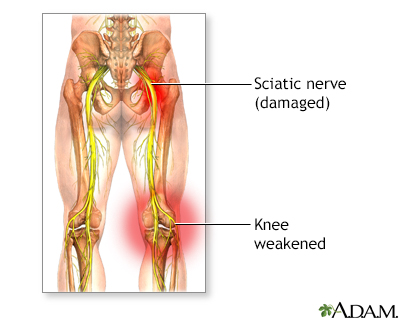

Download Sciatic nerve pain pictures